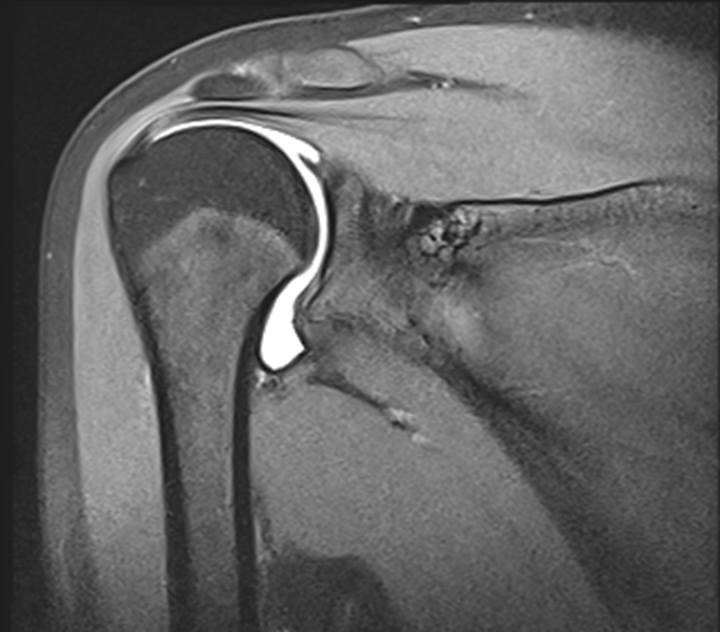

MRT Aufnahme des Schultergelenks mit intraartikulärer Injektion von Kontrastmittel (MR-Arthrographie) zur detaillierten Darstellung der Gelenk-Binnenstrukturen.